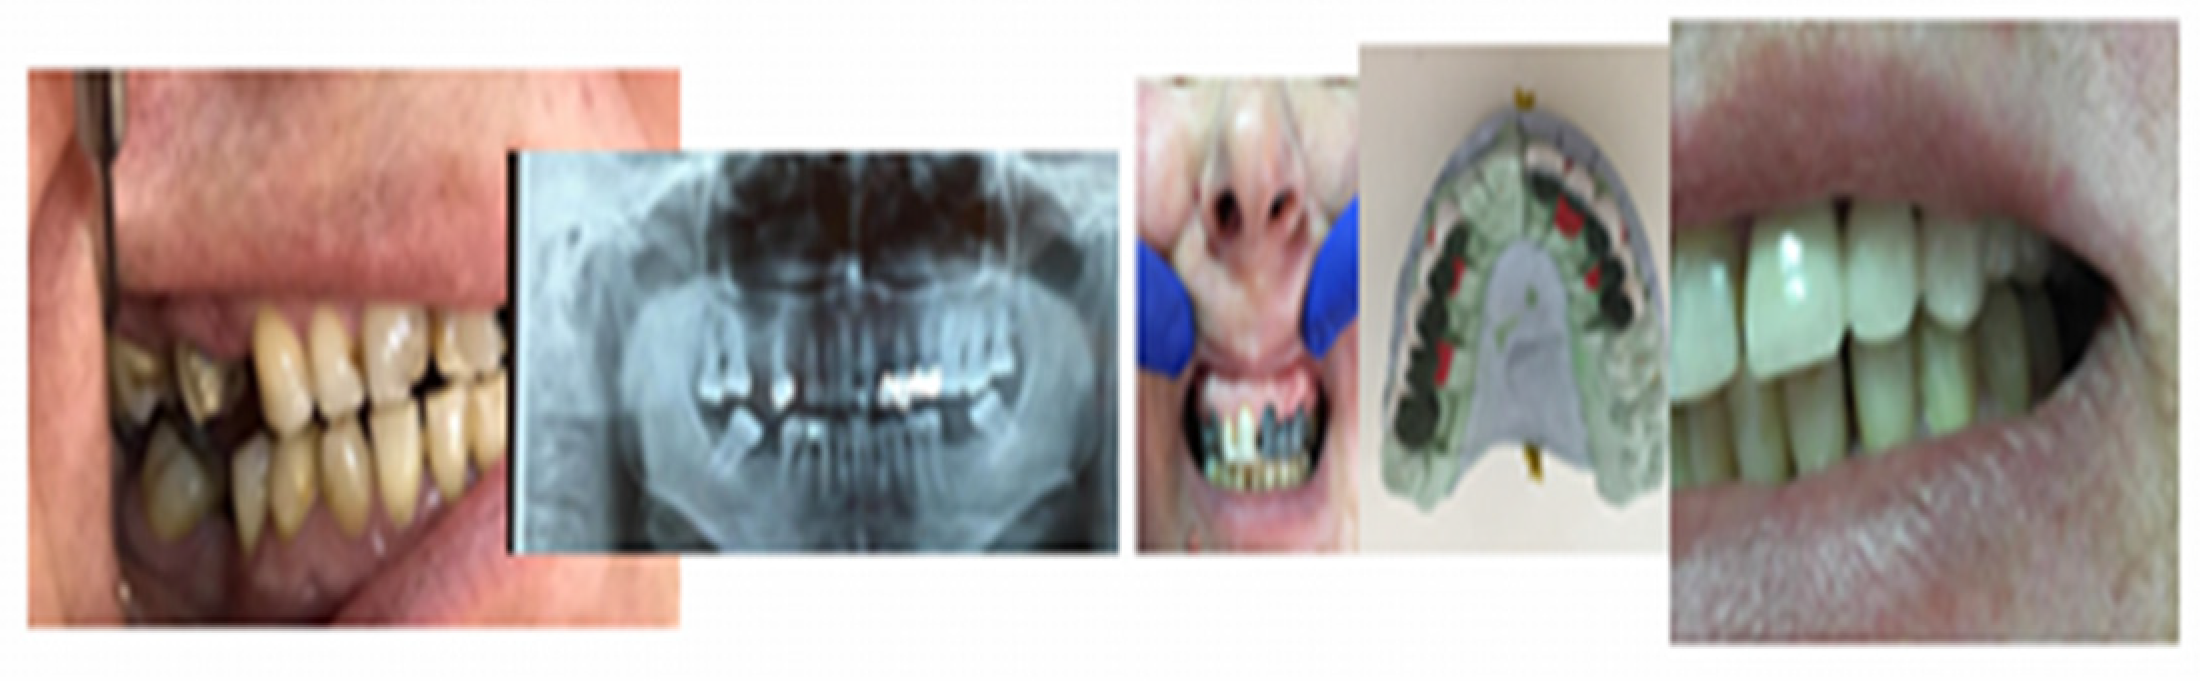

All kinds of specialized research on types of biomaterials used for endodontic restorations consider in the end the benefit of the patients, ensuring good biocompatibility, integration, stability, and functionality so that the predictable prosthetic rehabilitation increases quality of life by a proportion of 95% for the patients. Unidental restoration and Richmond crown result in an increase of 45%, and double prosthetic pieces elements result in an increase of 32% in a multiple construction bridge. A special importance can be observed in the approach of patients who presented clinical signs of dysfunctional syndrome in 25% who experienced pain, 15% with clinical signs of joint cracks and crepitation, and muscle dysfunctions in 35%, all due to occlusal imbalances, which require treatment with mouth guards and balneal–physical–kinetic therapy rehabilitation complex treatment in order to accomplish the principles of homeostasis and its stability [18,19,20] (Figure 13).

Figure 13. Images of the initial clinical situation, paraclinical orthopantomography examination, and the occlusal rehabilitation for the necessary foundation of the stomatognathic system homeostasis.